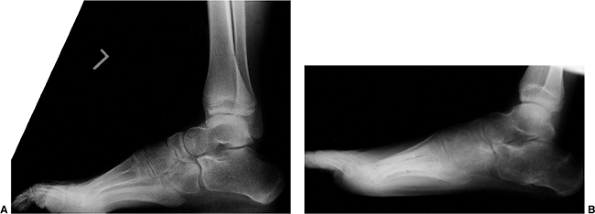

progresses (Fig. 17.3). Pseudohypertrophy of the calf is common, and eventually equinus and cavus foot deformities develop (Fig. 17.4).

associated with Becker muscular dystrophy is essentially the same as in

strength (141). Ankle and forefoot equinus occur commonly. Shapiro and Specht (6)

Forefoot equinus may require a plantar release and possibly a midfoot

dorsal-wedge osteotomy for correction. The use of orthotics is also